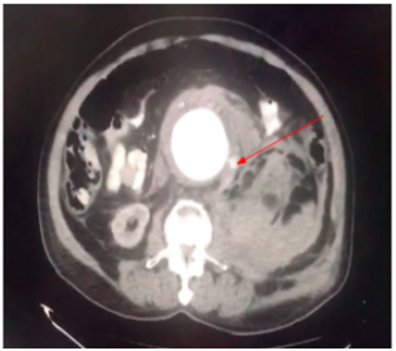

Posterior al ingreso, el paciente presenta un cuadro de lipotimia, con una tensión arterial de 82/41 mm/Hg, por lo cual se considera pasar un bolo de Lactato de Ringer de 2000 cc. Al cual el paciente responde favorablemente. Al examen físico, en la palpación abdominal se aprecia defensa voluntaria en flanco izquierdo, asociada a distensión, sin signos de irritación peritoneal. Por lo anterior se decide realizar una tomografía computarizada (TC) abdominal con contraste, la cual muestra un hematoma expansivo retroperitoneal en la zona II izquierda, secundario a AAA infrarrenal roto, asociado a un escape activo, con fuga hacia la zona II y con compromiso bilateral de las arterias iliacas (figura 1).